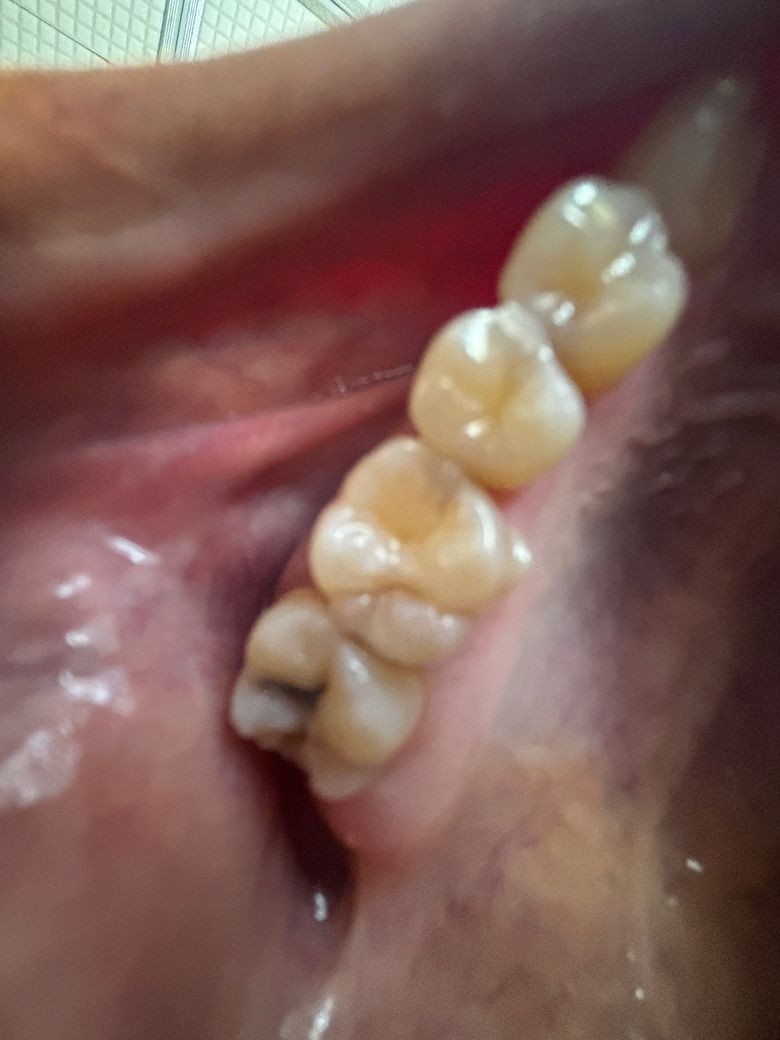

맨 뒤쪽 치아가 썩은 건가요??(사진첨부, 주의!!!)

맨 뒤쪽 검은 부분은 치아 썩은 건가요??

사진이 흐릿한 점 감안하고 답변부탁드립니다

• 1번 째 사진